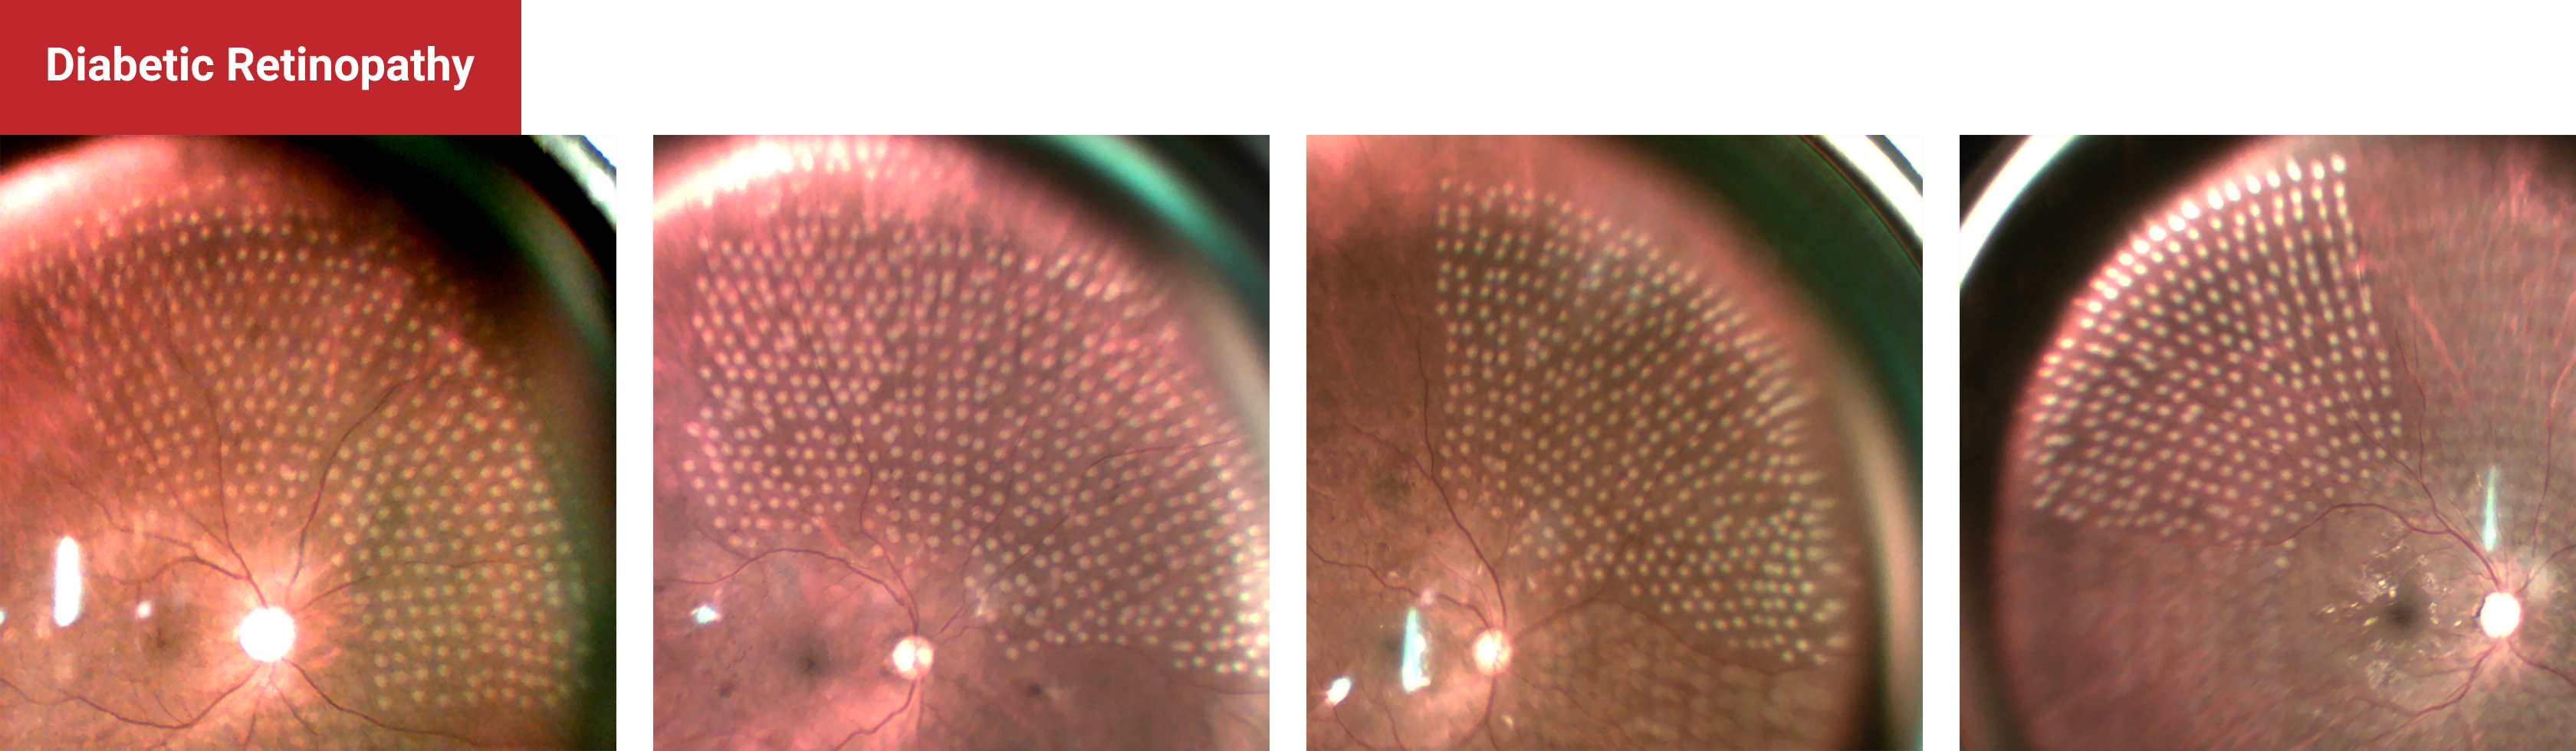

Diabetic Retinopathy

Pan Retinal Photocoagulation